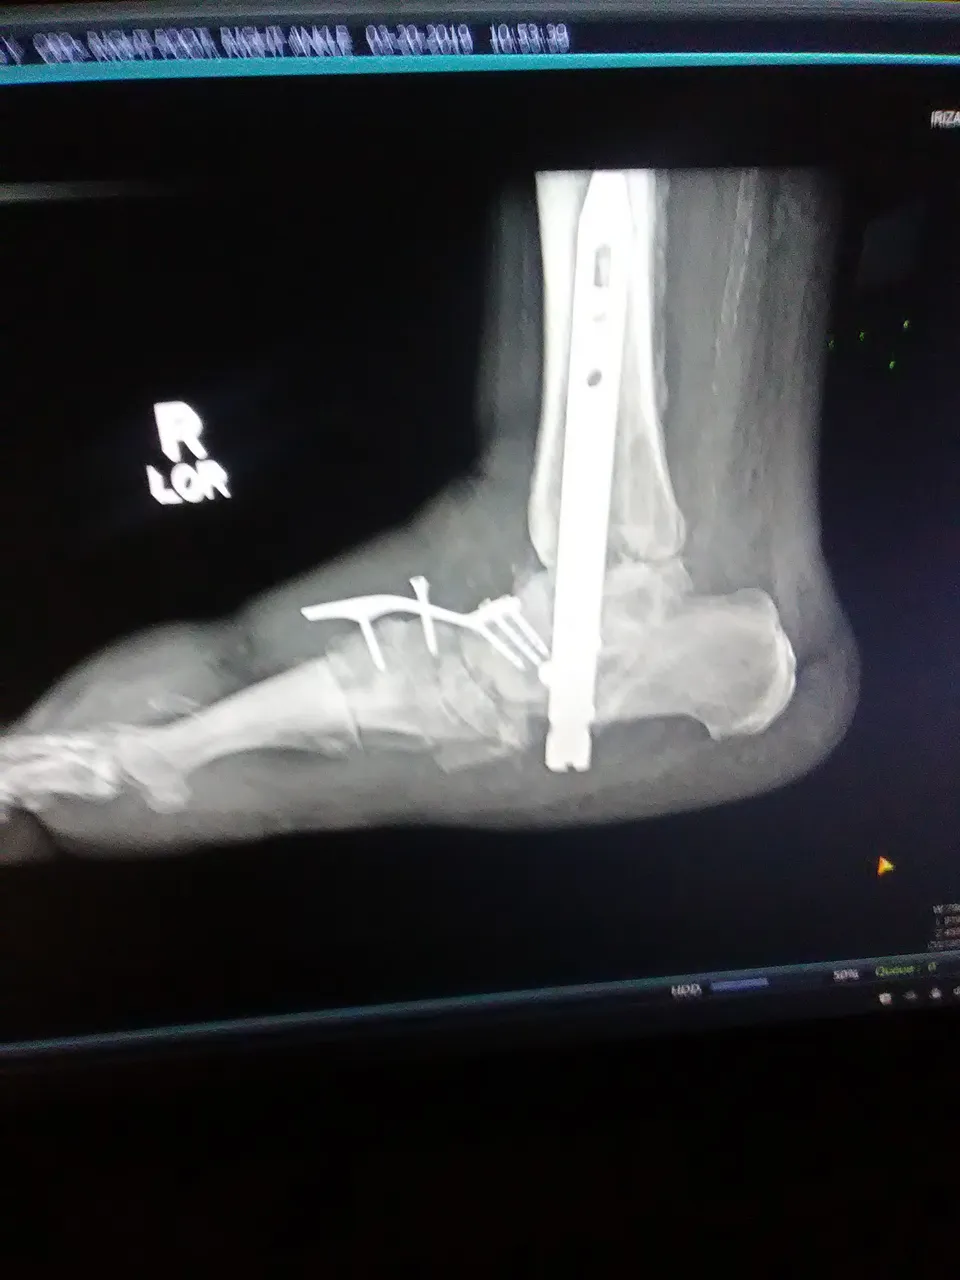

I developed a debilitating condition known as Charcot foot because of my condition of type 2 diabetes and diabetic neuropathy. At some point I suffered a blow to the foot that caused a fracture and having no sensation of pain in the foot I kept walking with it. By the time I noticed and I was able to go to a specialist I had several fractures in my foot. Now I have more screws than a hardware store in the foot, a special orthopedic boot (crowboot) that I have to use for life and restrictions that incapacitate me for most of the jobs I can find.